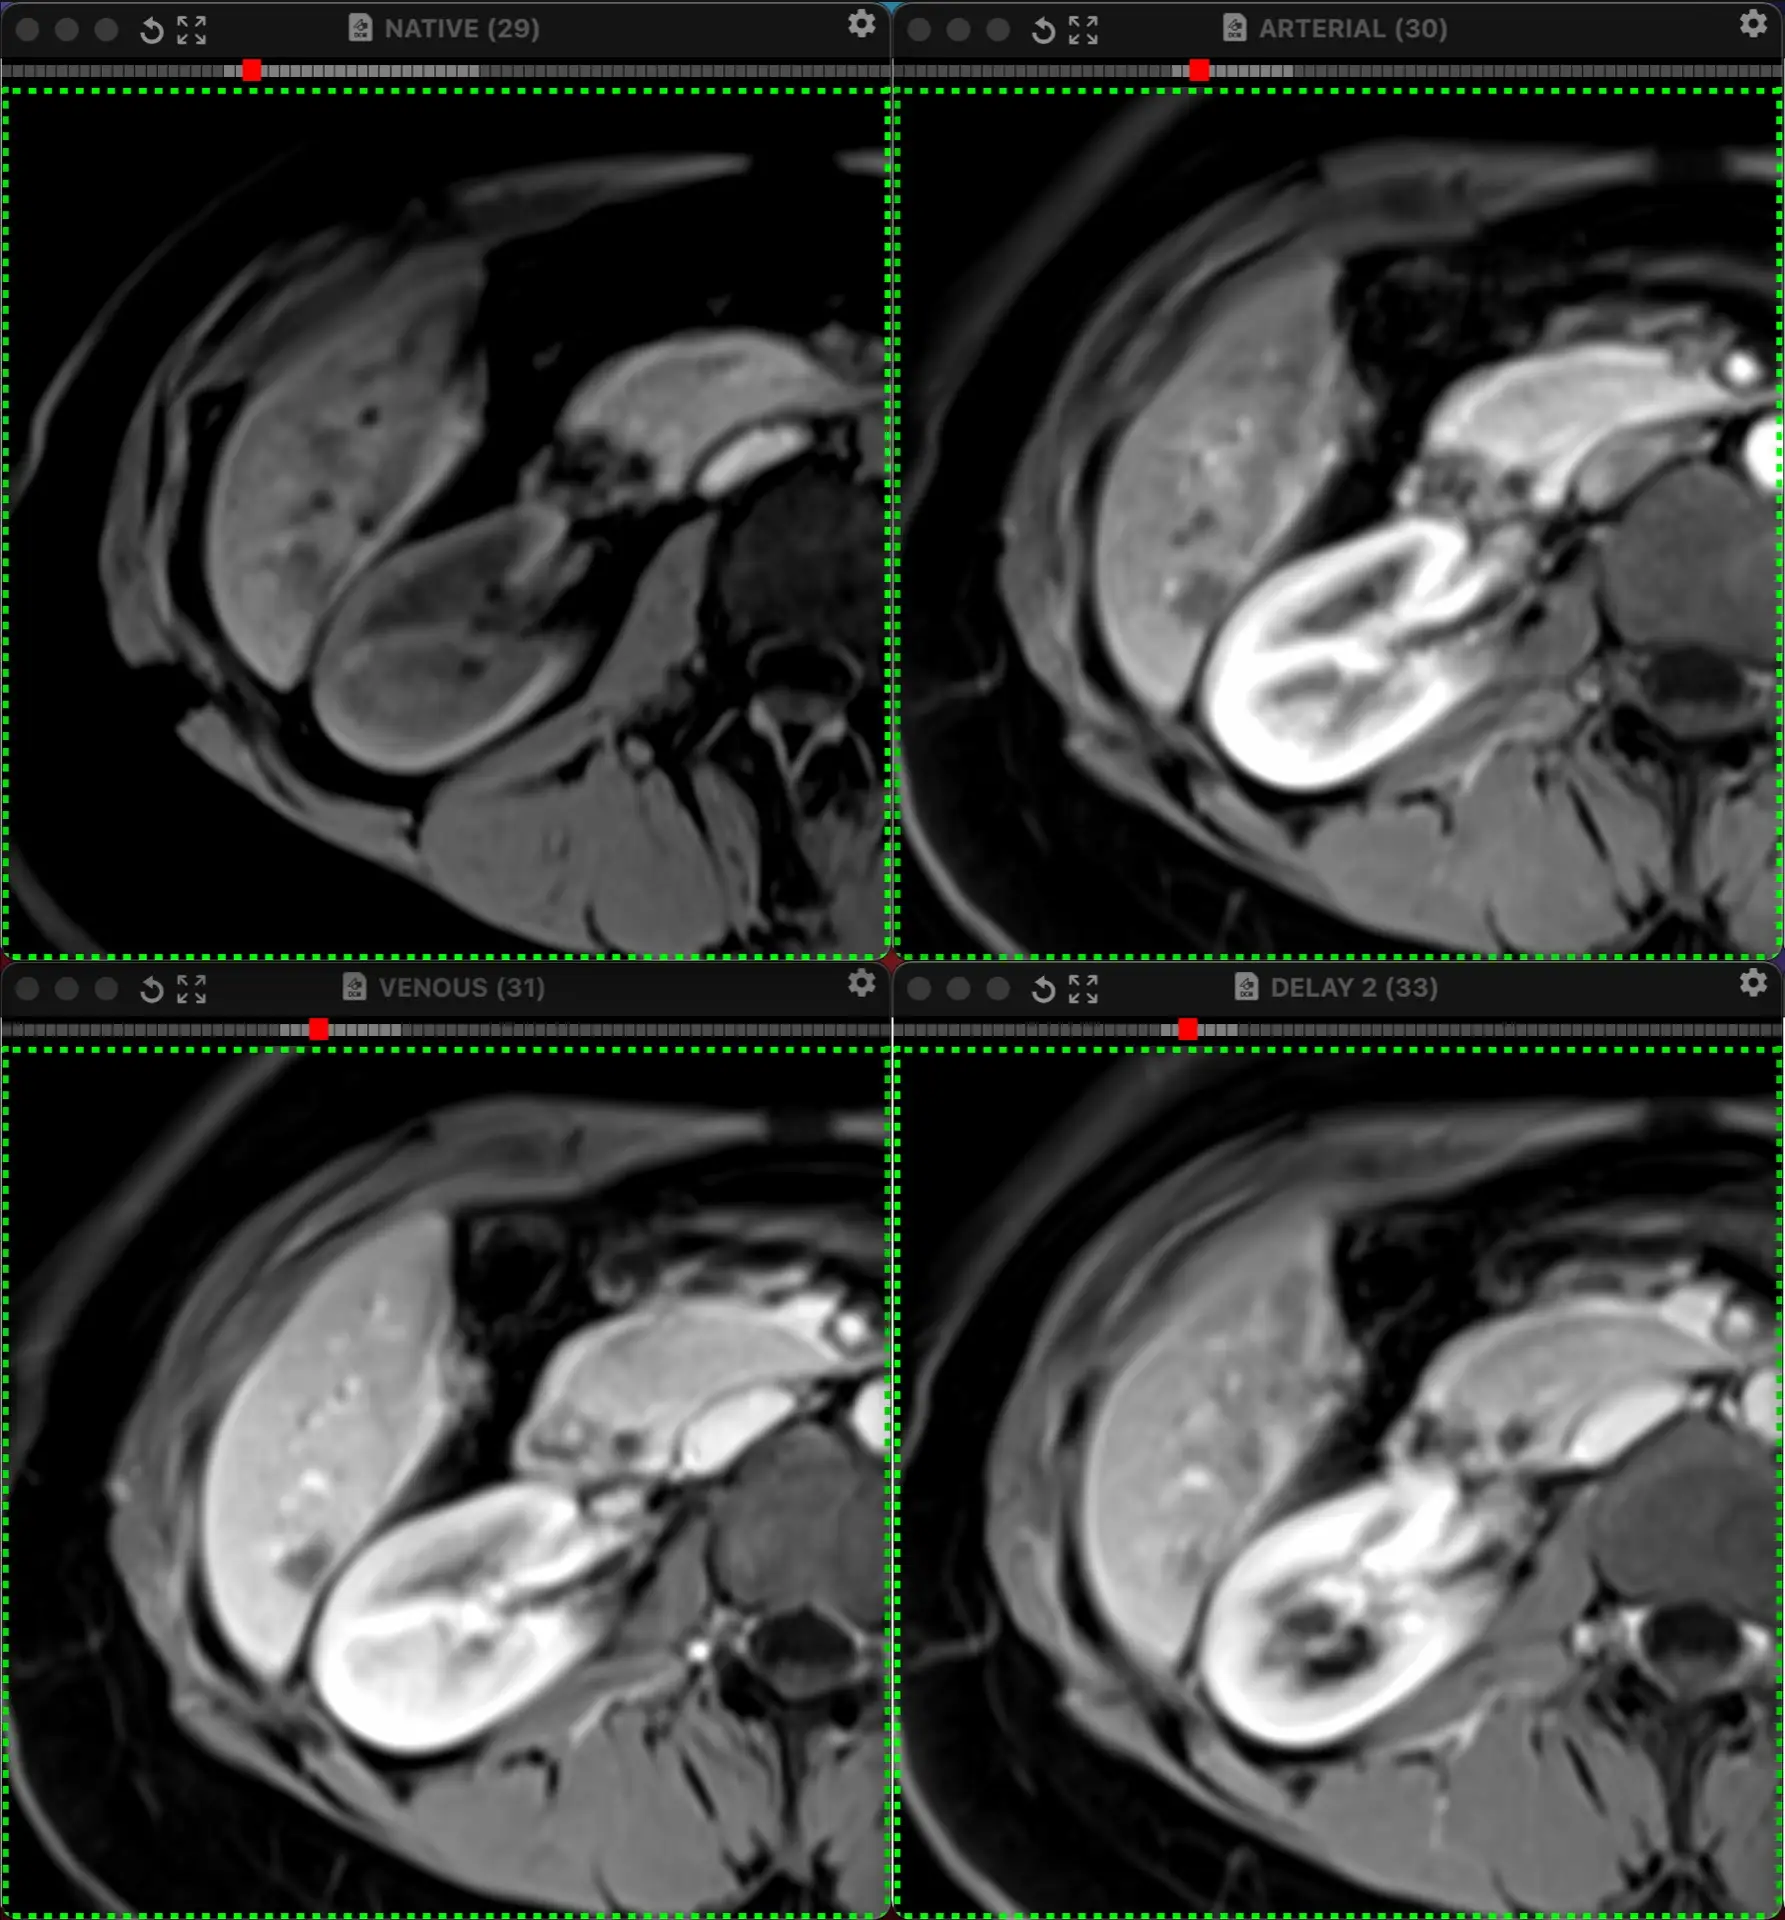

ЖЕНЩИНА 38 лет, фокальное изменение печени выявлено на УЗИ.

Повторные #КТ (с разницей в 2,5 месяца) без динамики. Имеется медленное, постепенное, слабоинтенсивное накопление контраста от периферии к центру.

На #МРТ - очень высокий сигнал на Т2, низкий на Т1, «лучистые» контуры. Истинное ограничение диффузии (ADC=460±109х10-6 кв.мм/с). Накопление контраста такое же, но на МРТ лучше видны краевое узелков накопление в артериальную фазу, тотального контрастирования нет даже на отсроченной фазе (через 5 минут).

Картина характерна: это гиалинизированная/ #склерозированнаягемангиома. Характерное стяжение контура является свидетельством склерозирования: уменьшения объёма, «рубцевания».

Гемангиомы с суженными кавернозными пространствами из-за склероза имеют большее количество более толстых и неровных перегородок, которые могут препятствовать диффузии молекул, что приводит к снижению значений ADC.

Склерозированные гемангиомы печени — это редкие доброкачественные поражения, которые часто трудно отличить от злокачественных, ибо они не имеют типичных для кавернозных гемангиом признаков.

Но! Часть признаков все равно сохраняются:

1. Значительный гиперсигнал на т2

2. Резкие, хоть и неровные, контуры

3. Центрипетальное, и иногда с приставочными узелками накопления контраста на артериальной фазе, контрастирование, пусть и неполное.

4. Стабильность в динамике